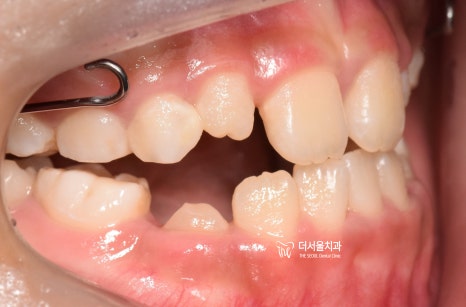

"상황이 더 나빠졌네요."

근데, 여기 단계까지 왔다가 결국

보호자와 환자는 서울대 치과병원으로 갔습니다.

근데, 거기서 교정을 할 수 없다는 판단하게

돌고 돌아서 결국 다시 저에게 오셨는데

그 기간이 꽤나 기셨거든요?

치열이 다시 나빠져 있는 상태로

내원을 하셨었습니다.

아마.. 이 때 서울대로 가지 않고

성장교정 을 계속 진했더라면

더 수월했을텐데..